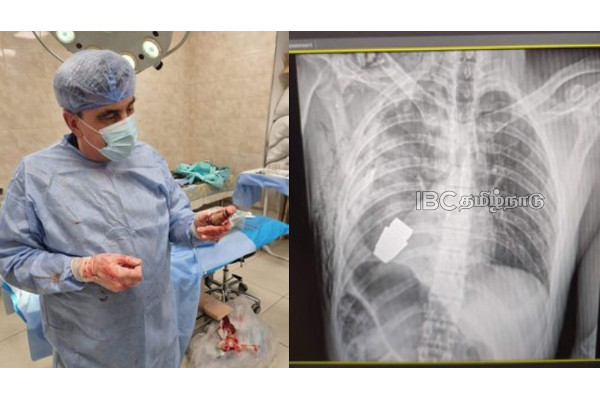

உக்ரைனில் ஒரு ராணுவ வீரரின் உடலில் இருந்து எந்த நேரத்திலும் வெடிக்கக்கூடிய VOG கையெறி குண்டுகளை மருத்துவர் ஒருவர் அறுவை சிகிச்சை மூலம் வெற்றிகரமாக அகற்றி உயிரை காப்பாற்றியுள்ளார்.

இந்த அறுவை சிகிச்சை எலெக்ட்ரோகோகுலேஷன் இல்லாமல் மேற்கொள்ளப்பட்டது. ஏனென்றால், கையெறி குண்டுகள் எந்த நேரத்திலும் வெடிக்கக்கூடும். ஆதலால் மிகவும் எச்சரிக்கையாக இந்த அறுவை சிகிச்சை மேற்கொண்டு ராணுவ வீரரின் உயிரை காப்பாற்றியுள்ளார்.

Ukraine’s military doctors successfully performed surgery to remove an unexploded VOG grenade from a serviceman’s body. AFU surgeon, major general Andriy Verba, worked without electrocoagulation, since grenade could detonate at any moment. Wow!!